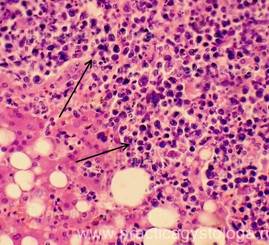

Рис. 3. Септический метастатический очаг острого гнойного межуточного миокардита с колониями бактерий. В окружающем миокарде обилие сливающихся друг с другом мелких очагов умеренной-выраженной фуксинофилии цитоплазмы кардиомиоцитов в виде мелких их участков, окрашенных в красный цвет на жёлто-зелёном фоне. Окраска: ГОФП-метод (по Ли). Увеличение х100, х250.